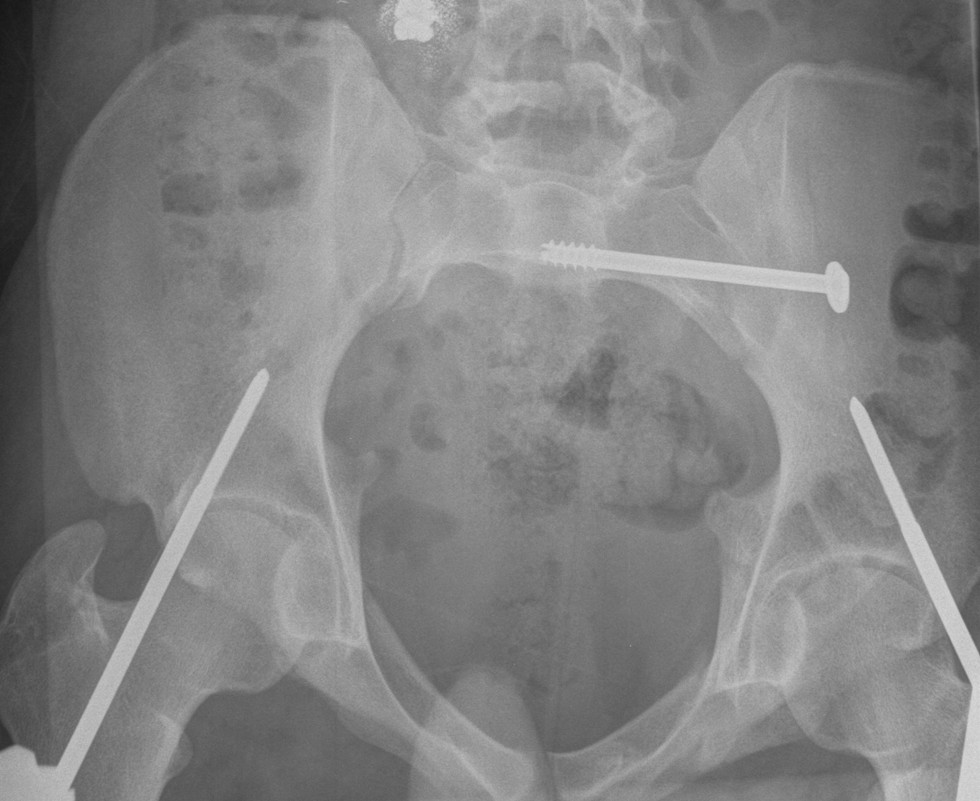

Guide wire insertion into body of S1

- anatomic safe zone

- between S1 foramen and superior ala on outlet view (outlet view)

- between neural canal and anterior body (inlet view)

Insert 6.5 mm partially threaded cannulated screw, to aid compression

Post operative

Check screw position with CT